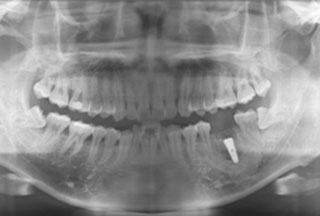

¹ßÄ¡ Áï½Ã ÀÓÇöõÆ® ÀüÈÄ»çÁø

½Ã¼ú Àü ¹æ»ç¼±»çÁø - 2

½Ã¼ú ÈÄ ¹æ»ç¼±»çÁø